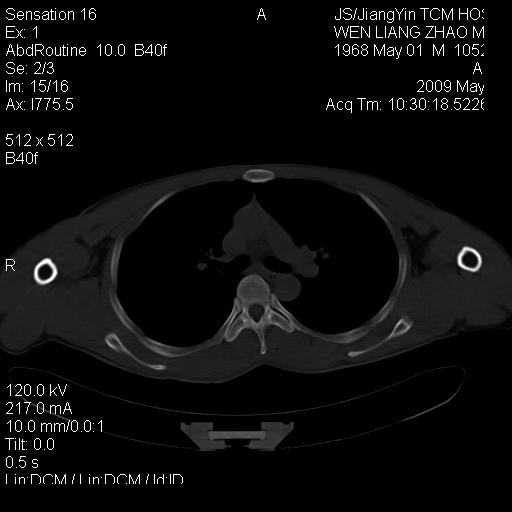

标题: CT19762:左侧喙突处压痛二年。考虑骨样骨瘤。 [打印本页]

标题: CT19762:左侧喙突处压痛二年。考虑骨样骨瘤。

左侧喙突处压痛二年。考虑骨样骨瘤。